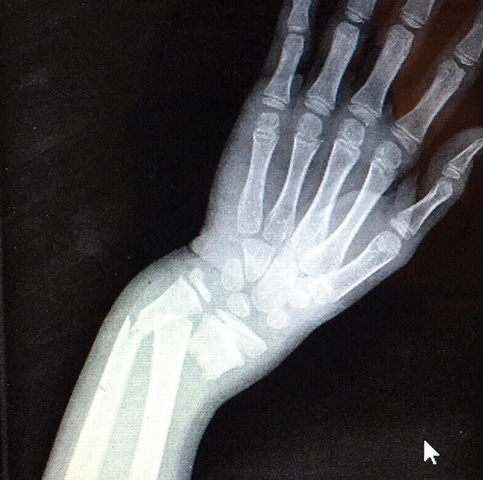

- Ενδεικτικά περιστατικά του Ιατρού

Χειρουργός ορθοπαιδικός παίδων

Νικόλαος Α. Λαλιώτης, M.Ch. Orth.

- Χειρουργός Ορθοπαιδικός - Master of Orthopaedic Surgery